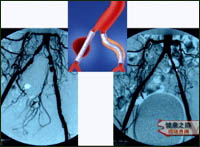

主持人:刚才那位患者采用的是什么治疗方法呢? 姜宏:我们在给患者进行血管造影检查时就已经开始治疗了,具体做的是局部溶栓治疗、超声消融治疗、球囊括张治疗,最后进行的是支架治疗。来看一张图患者最初人字形的三根大血管已经完全闭塞了,当时没有采用右图所示的搭桥手术,而是采用的微创治疗,难度是很大的。我们来看一个图示,这是一个超声消融导管,头端释放的能量可以把阻塞物打得很碎,治疗后血流仍然有影响,因此进行了球囊括张治疗,治疗后血管相对通畅了许多但是仍然达不到要求,因此又做了内支架植入。治疗完成后(如图所示)血管就非常通常了。 杨晓凤:患者治疗后还用了三天的药包括抗凝剂、血管活性药物、血管内膜修复剂。总的治疗时间大约需要十天左右。 患者:我现在恢复情况很好,走路甚至跑都没有什么问题。

主持人:烟台张先生 我长期吸烟,左脚凉,在医院做彩超,说是髂动脉硬化,还有一个动脉瘤,不想做手术,你们有什么办法? 姜宏:动脉瘤的治疗可以采用一种新的血管腔内的修补治疗。如图患者通过治疗后狭窄和动脉瘤都消失了。

主持人:南宁何女士 我哥哥48岁,一周前左小腿突然明显发凉、疼痛,在医院检查,医生说是腘动脉血栓,需要溶栓治疗,但他有风心病,彩超检查说心房内有血栓,不能溶栓,该怎么办? 姜宏:患者现在应该马上做超声消融治疗,来看一张图,患者的动脉血管在腘动脉的位置已经中断了,通过超声消融治疗后血流恢复了,管腔也非常通畅了。